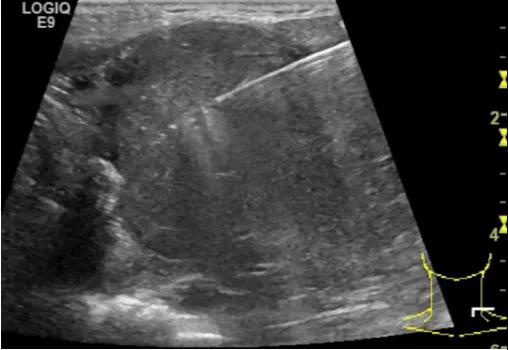

第三例是甲状腺癌患者,双侧甲状腺癌切除术后、碘治疗后一年余效果欠佳,超声显示左颈3区3枚低回声结节,穿刺示甲状腺乳头状癌转移。患者不愿意手术,希望采取局部治疗。对病灶进行液体隔离后采取热消融术,由于淋巴结较小,热消融一分钟左右完全灭活,术后增强影像显示没有脏器充填。

(病例3图例)